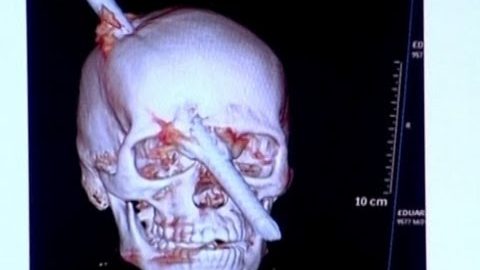

Survived, After he pinned metal bar on head

Incredible accident of 24-year-old Brazilian Eduardo Leite, that during his work in the construction of a building in Rio de Janeiro a metal bar fell from the 5th floor and pinned on his head. Was rushed to hospital where doctors normally spoke, After removing the rod in the operating room is perfectly healthy.